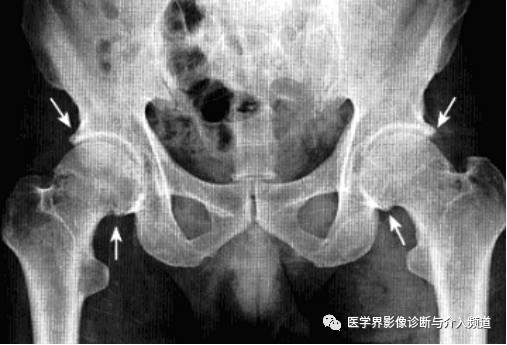

强直性脊柱炎累及髋关节

系累及中轴骨及近端大关节的血清阴性脊柱关节病。病变对称侵及骶髂关节、椎间小关节、附件韧带和近躯干的大关节,最后导致纤维性或骨性强直和畸形。髋关节是本病最常累及的关节,约占50%。

影像诊断:X线片为主要检查手段,MRI能显示早期髋关节改变。

1、平片:双侧对称受累,早期骨质疏松,关节囊膨隆,股骨头及髋臼骨质侵蚀糜烂;中期关节间隙一致性狭窄,软骨下囊性变,关节面边缘骨质增生,坐骨结节、坐骨耻骨支及股骨大转子可伴骨膜炎;晚期股骨头内移、髋臼内突,关节腔闭锁呈骨性强直。

2、CT:早期少量关节腔积液,可伴髂腰肌囊扩张,同时股骨头骨质疏松,股骨头及髋臼缘囊状、虫蚀状骨质缺损;中期关节面边缘硬化、囊变、骨赘形成,股骨头基底滑膜附着处增生,髋关节间隙均匀一致性狭窄消失,双侧髋对称性骨性强直,股骨头及髋臼可普遍性肥大。

3、MRI:①关节积液,关节间隙增宽,②滑膜增厚,增强后明显强化,③关节软骨水肿,④关节面软骨信号改变,炎性血管翳增生,信号强度不均,⑤软骨下囊性变,⑥关节骨性强直。